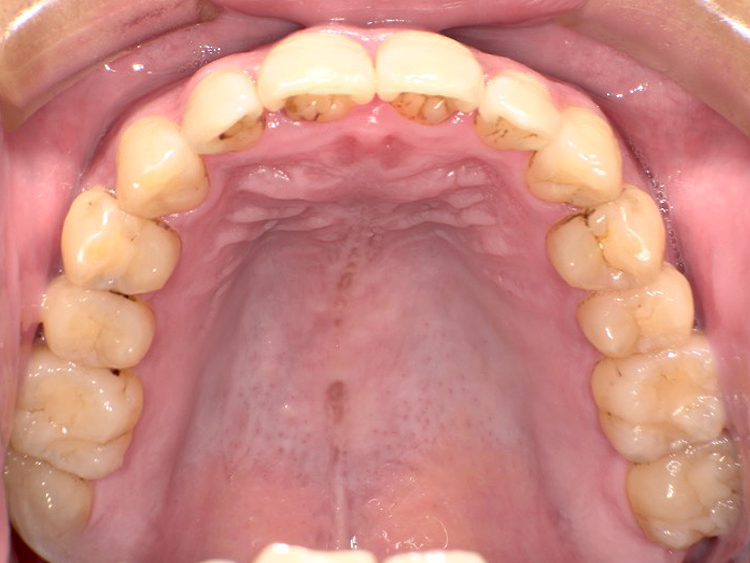

症例5

Before

After

| 主訴 | 上下3-3の並びが気になる |

|---|---|

| 年齢 | --- |

| 治療 期間 |

約1年 |

| 治療 内容 |

インビザライン5-5 |

| 治療費 | ¥517,000(税込)/調整料含む |

| 治療のリスク | 奥歯を動かさないので、前に出して並べていく。 歯と歯が移動するスペースを作るので、知覚過敏の症状がまれにでる。 歯を動かすことで、歯茎が下がるリスクある。 矯正終了後は、リテーナーを使用し、後戻りを防ぐ必要がある。 |